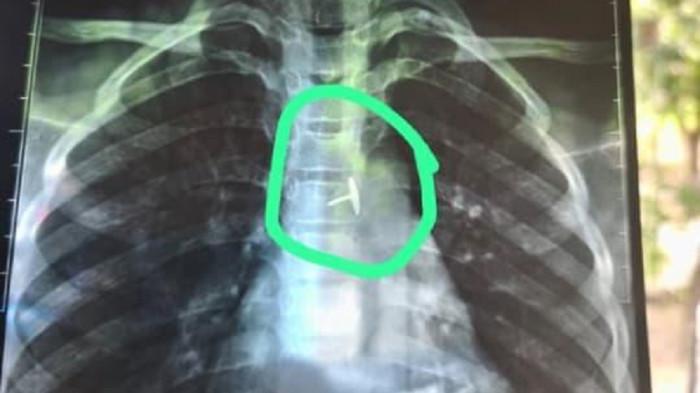

SURYAMALANG.COM, BOJONEGORO - Jagat maya dihebohkan dengan beredarnya foto hasil rontgen diduga milik seorang bocah SD di Kabupaten Bojonegoro, Jawa Timur.

Dalam foto yang viral di media sosial Instagram itu, tampak jelas sebuah benda asing berbentuk paku pines bersarang di dalam kerongkongan sang bocah.